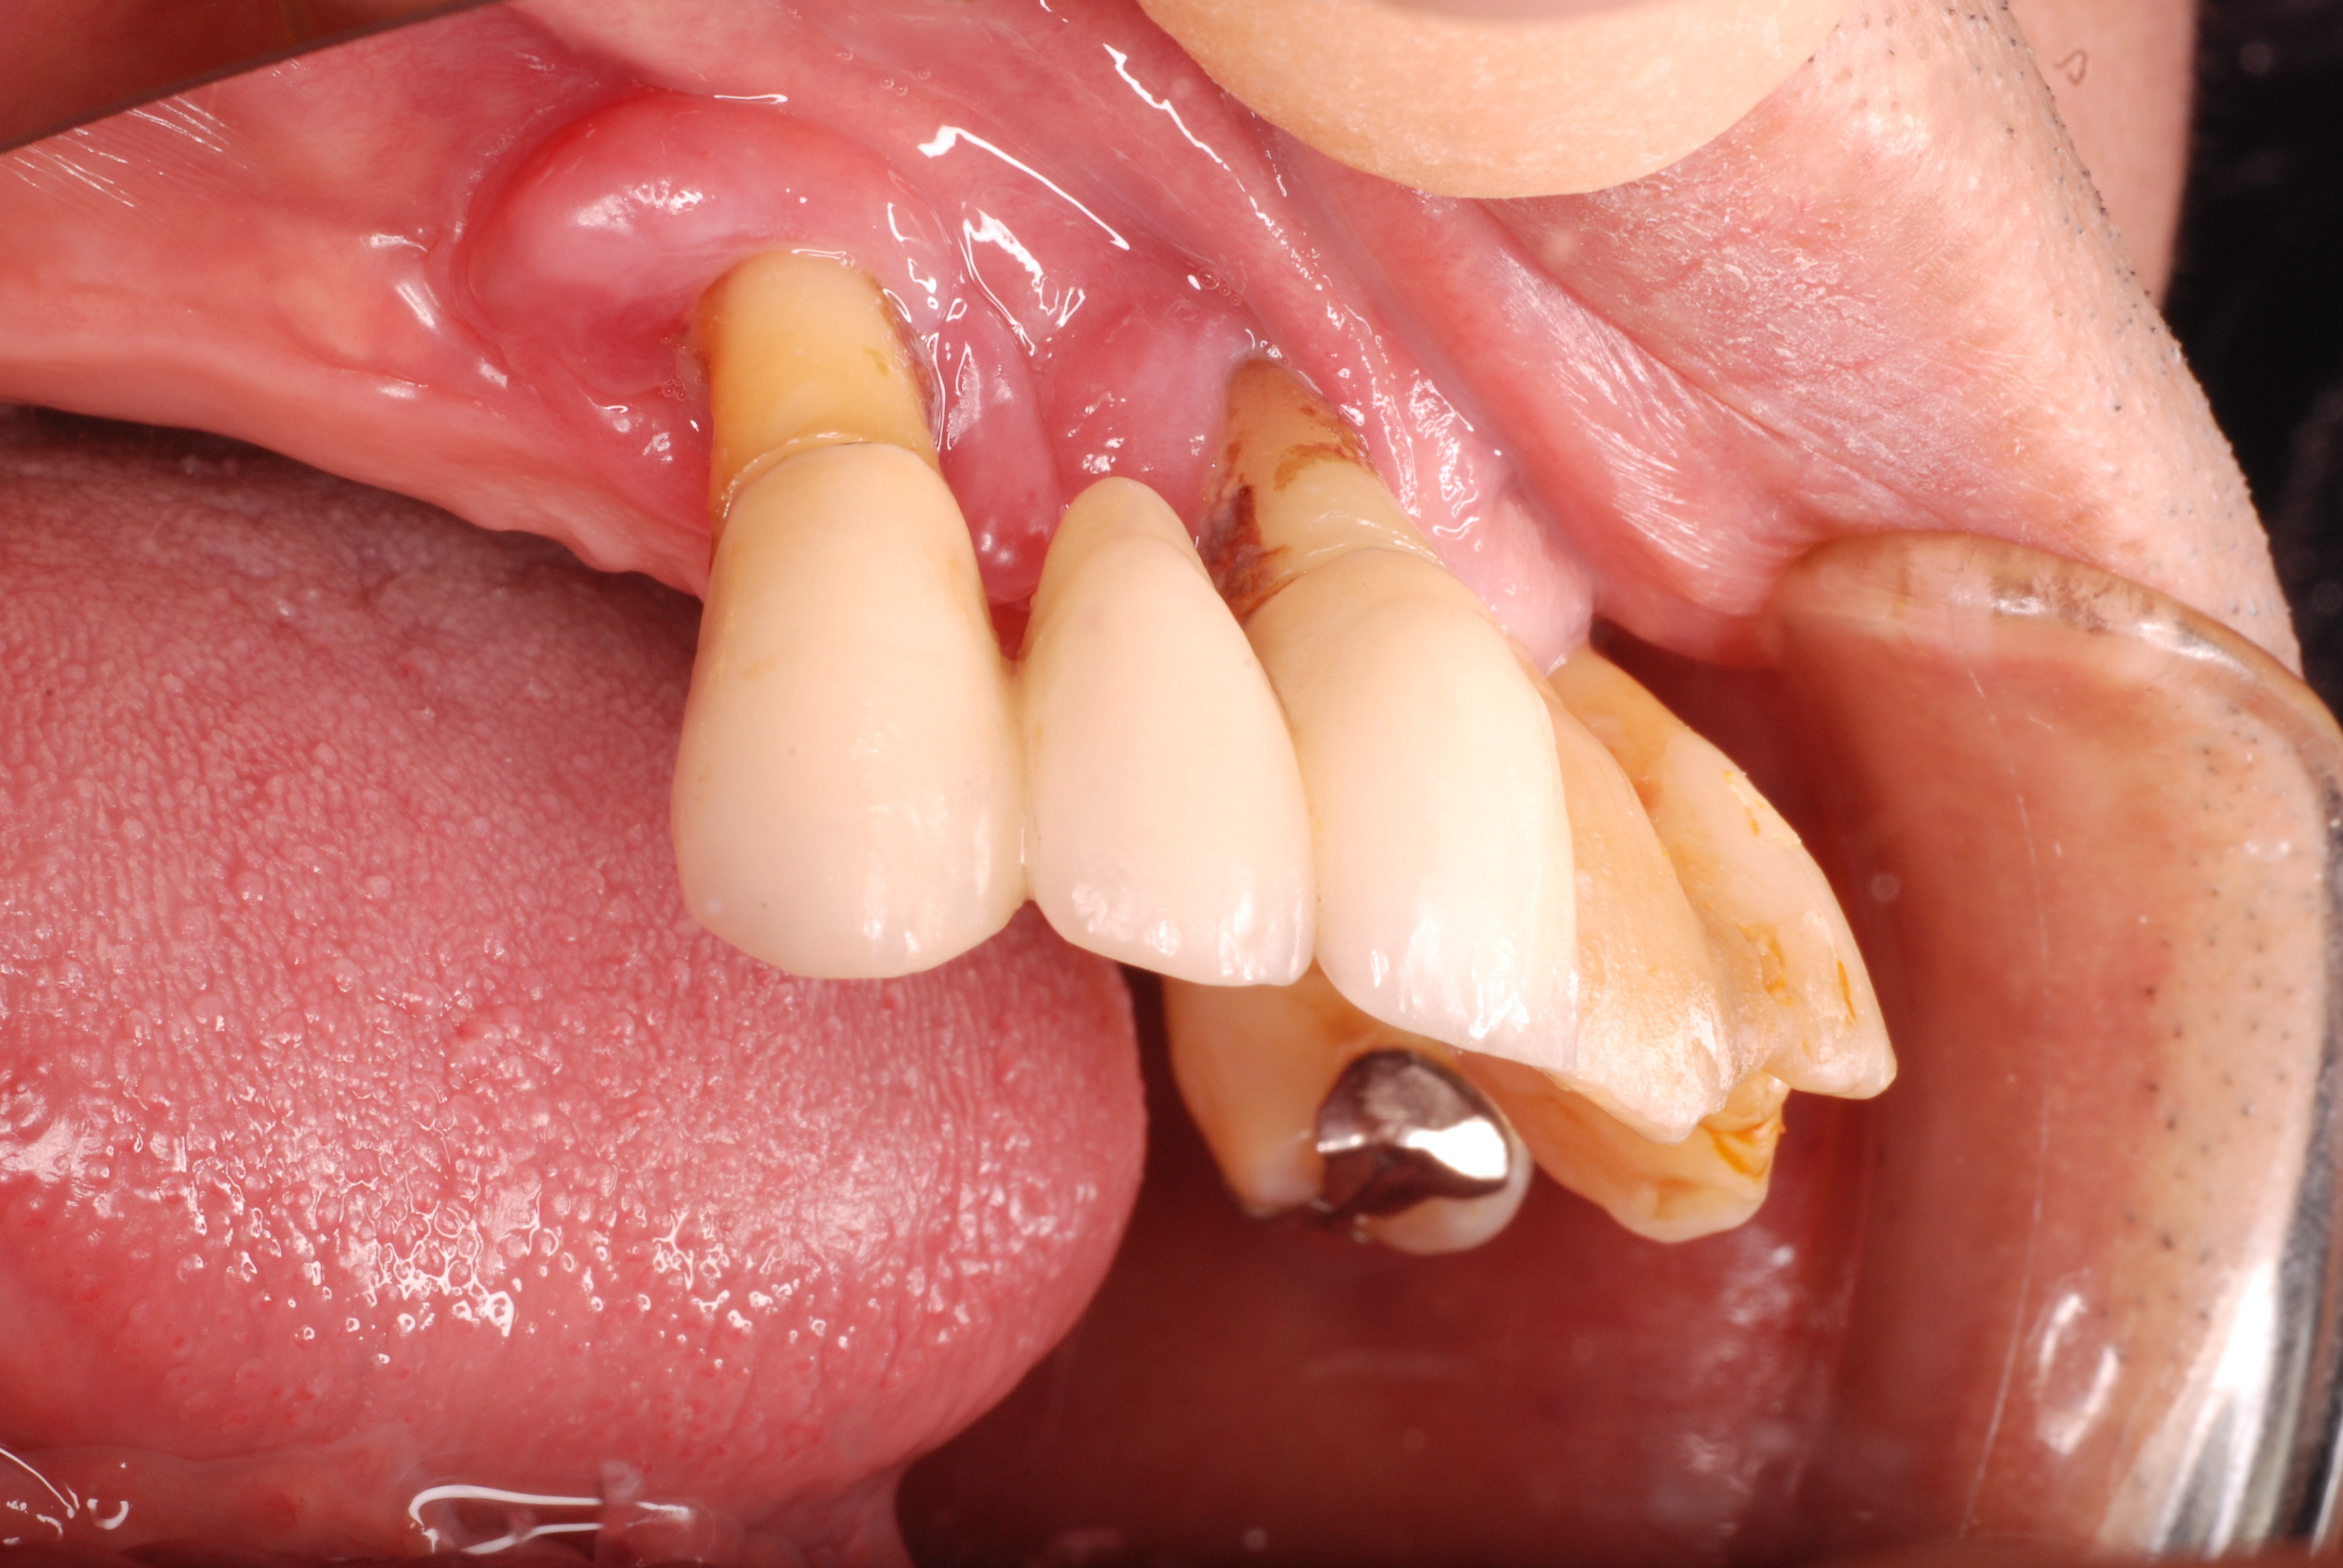

お口の中には高価なセトモノや金歯が多いのですが、

残念ながら健康になったわけではないのです。

分岐部の歯周病を見逃した為に頬が腫れあがり診察の結果、

歯の歯折か重症の分岐部の歯周病と判断した患者さんです。

検査の為に歯茎を開き少し悪いところを取って様子を見ていたのですが、又激痛が走りその為応急処置として東洋医学で対処しました。

ですが、根本的に悪いところを取らなくては再発するだけでなく歯そのものが駄目になる事をお話しして納得してもらい、セラミックを外しその後重症の分岐部の歯周病と判断して歯の一部分と悪い病気の歯肉をえぐりとったその後1週間後の写真です。

DSC_0012右上の奥から2番目の歯が問題の歯です。

セトモノが入っていますが、だからと言って健康になったわけではないのです。切り取った歯の残りと切り取り後が痛々しいですね。